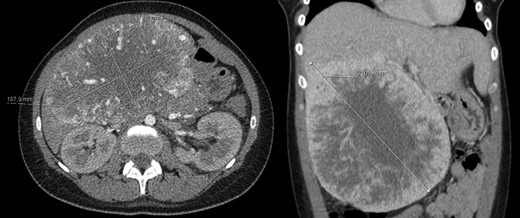

A 40-year-old woman with past medical history of c-section at the age of 26, was referred to our Hepatobiliary Unit in 2013, with diagnose of liver tumor with 16.6 cm (Fig. 2) suggestive of solitary fibrous tumor.

Abdominal Magnetic Resonance – heterogeneous liver mass in segment 4 with 16.6 cm.

No distant metastasis was identified.